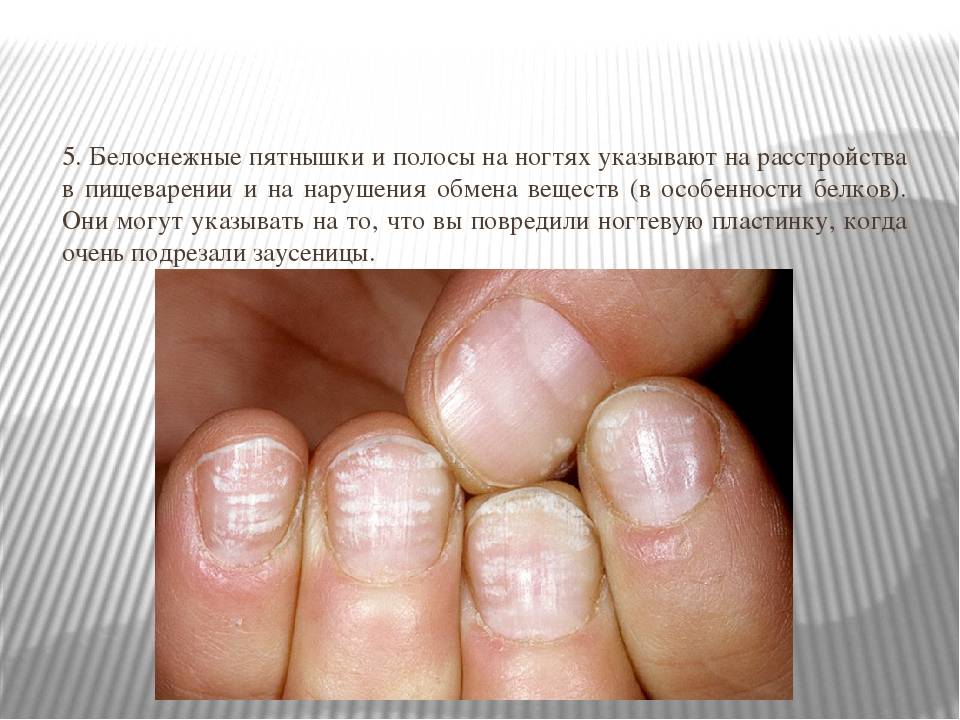

Грибковые заболевания ногтей: буклет с информацией